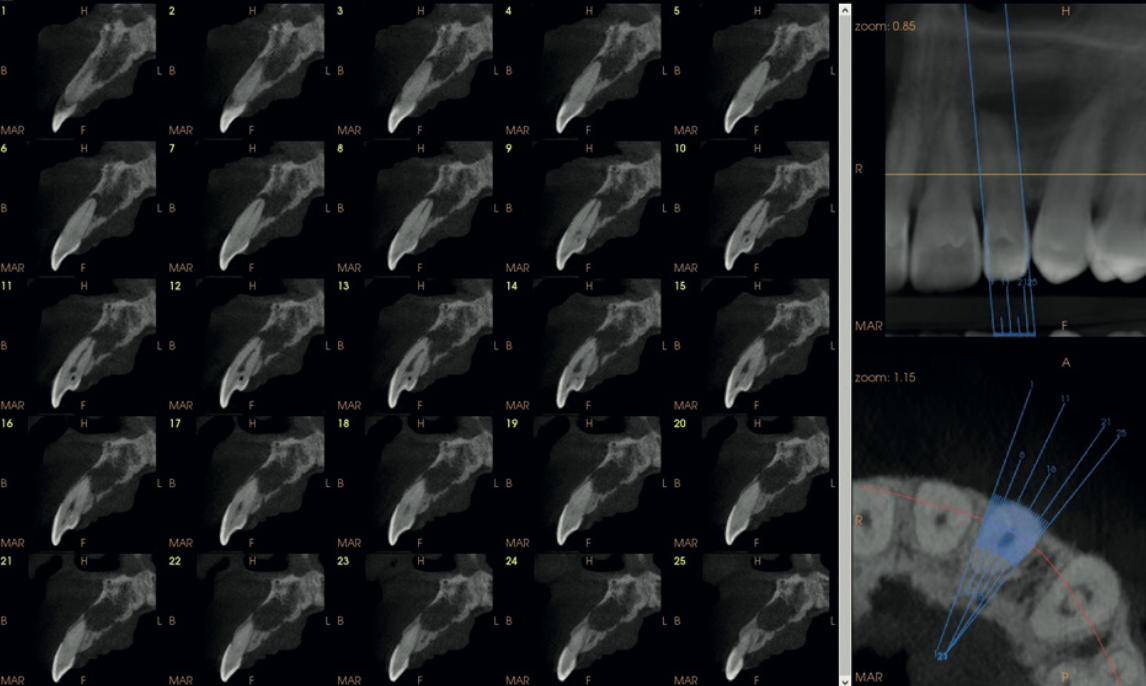

Multiplanar CBCT view of UL2 with enlarged sagittal showing the invagination course through the tooth

Fig. 3 Multiplanar CBCT view of UL2 with enlarged sagittal section revealing the full course of the dens invaginatus — extending from the crown through to the root apex.

The scan also showed focal calcification in the coronal third of the main root canal, with the canal space dilated in the middle third and well-visualised calibre in the remainder. Thin cross-sectional slices mapped the full morphological complexity of the tooth.

Thin serial cross-sections of UL2 from the CS 9600 CBCT showing the dens invaginatus morphology at 75 micron resolution

Fig. 4 Serial thin cross-sections of UL2 at 75-micron resolution. The invagination and its relationship to the main canal and root morphology are clearly delineated — impossible to achieve on a periapical radiograph.